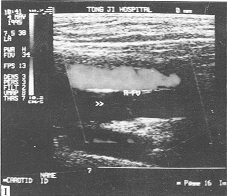

图1 Vasalva's动作 股浅动脉呈红色显示。箭头:关闭的股浅静脉瓣。股静脉、股浅静脉、股深静脉内无血流显示

图2

静脉第一对瓣口处血流返流。蓝色为正常

静脉血流。红色为瓣口处反向血流